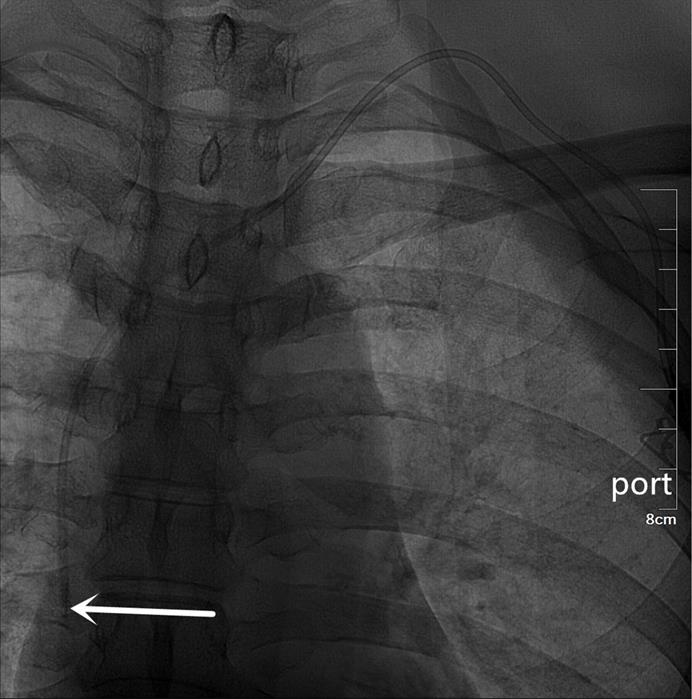

The US probe was run down the IJV (Figure 1) to the top of the sternoclavicular joint to obtain a longitudinal view of the BCV. The puncture site was locally anesthetized with 1% lidocaine. With the guidance of the US probe (the in-plane technique), the needle was advanced once the BCV was visualized on the US screen (Figure 2). After successful puncture, the guide wire, sheath, and catheter were entered sequentially.

Figure 1

The ultrasound probe runs down the IJV showing the outboard IJV and the inboard CCA. IJV indicates the internal jugular vein; CCA indicates the common carotid artery.